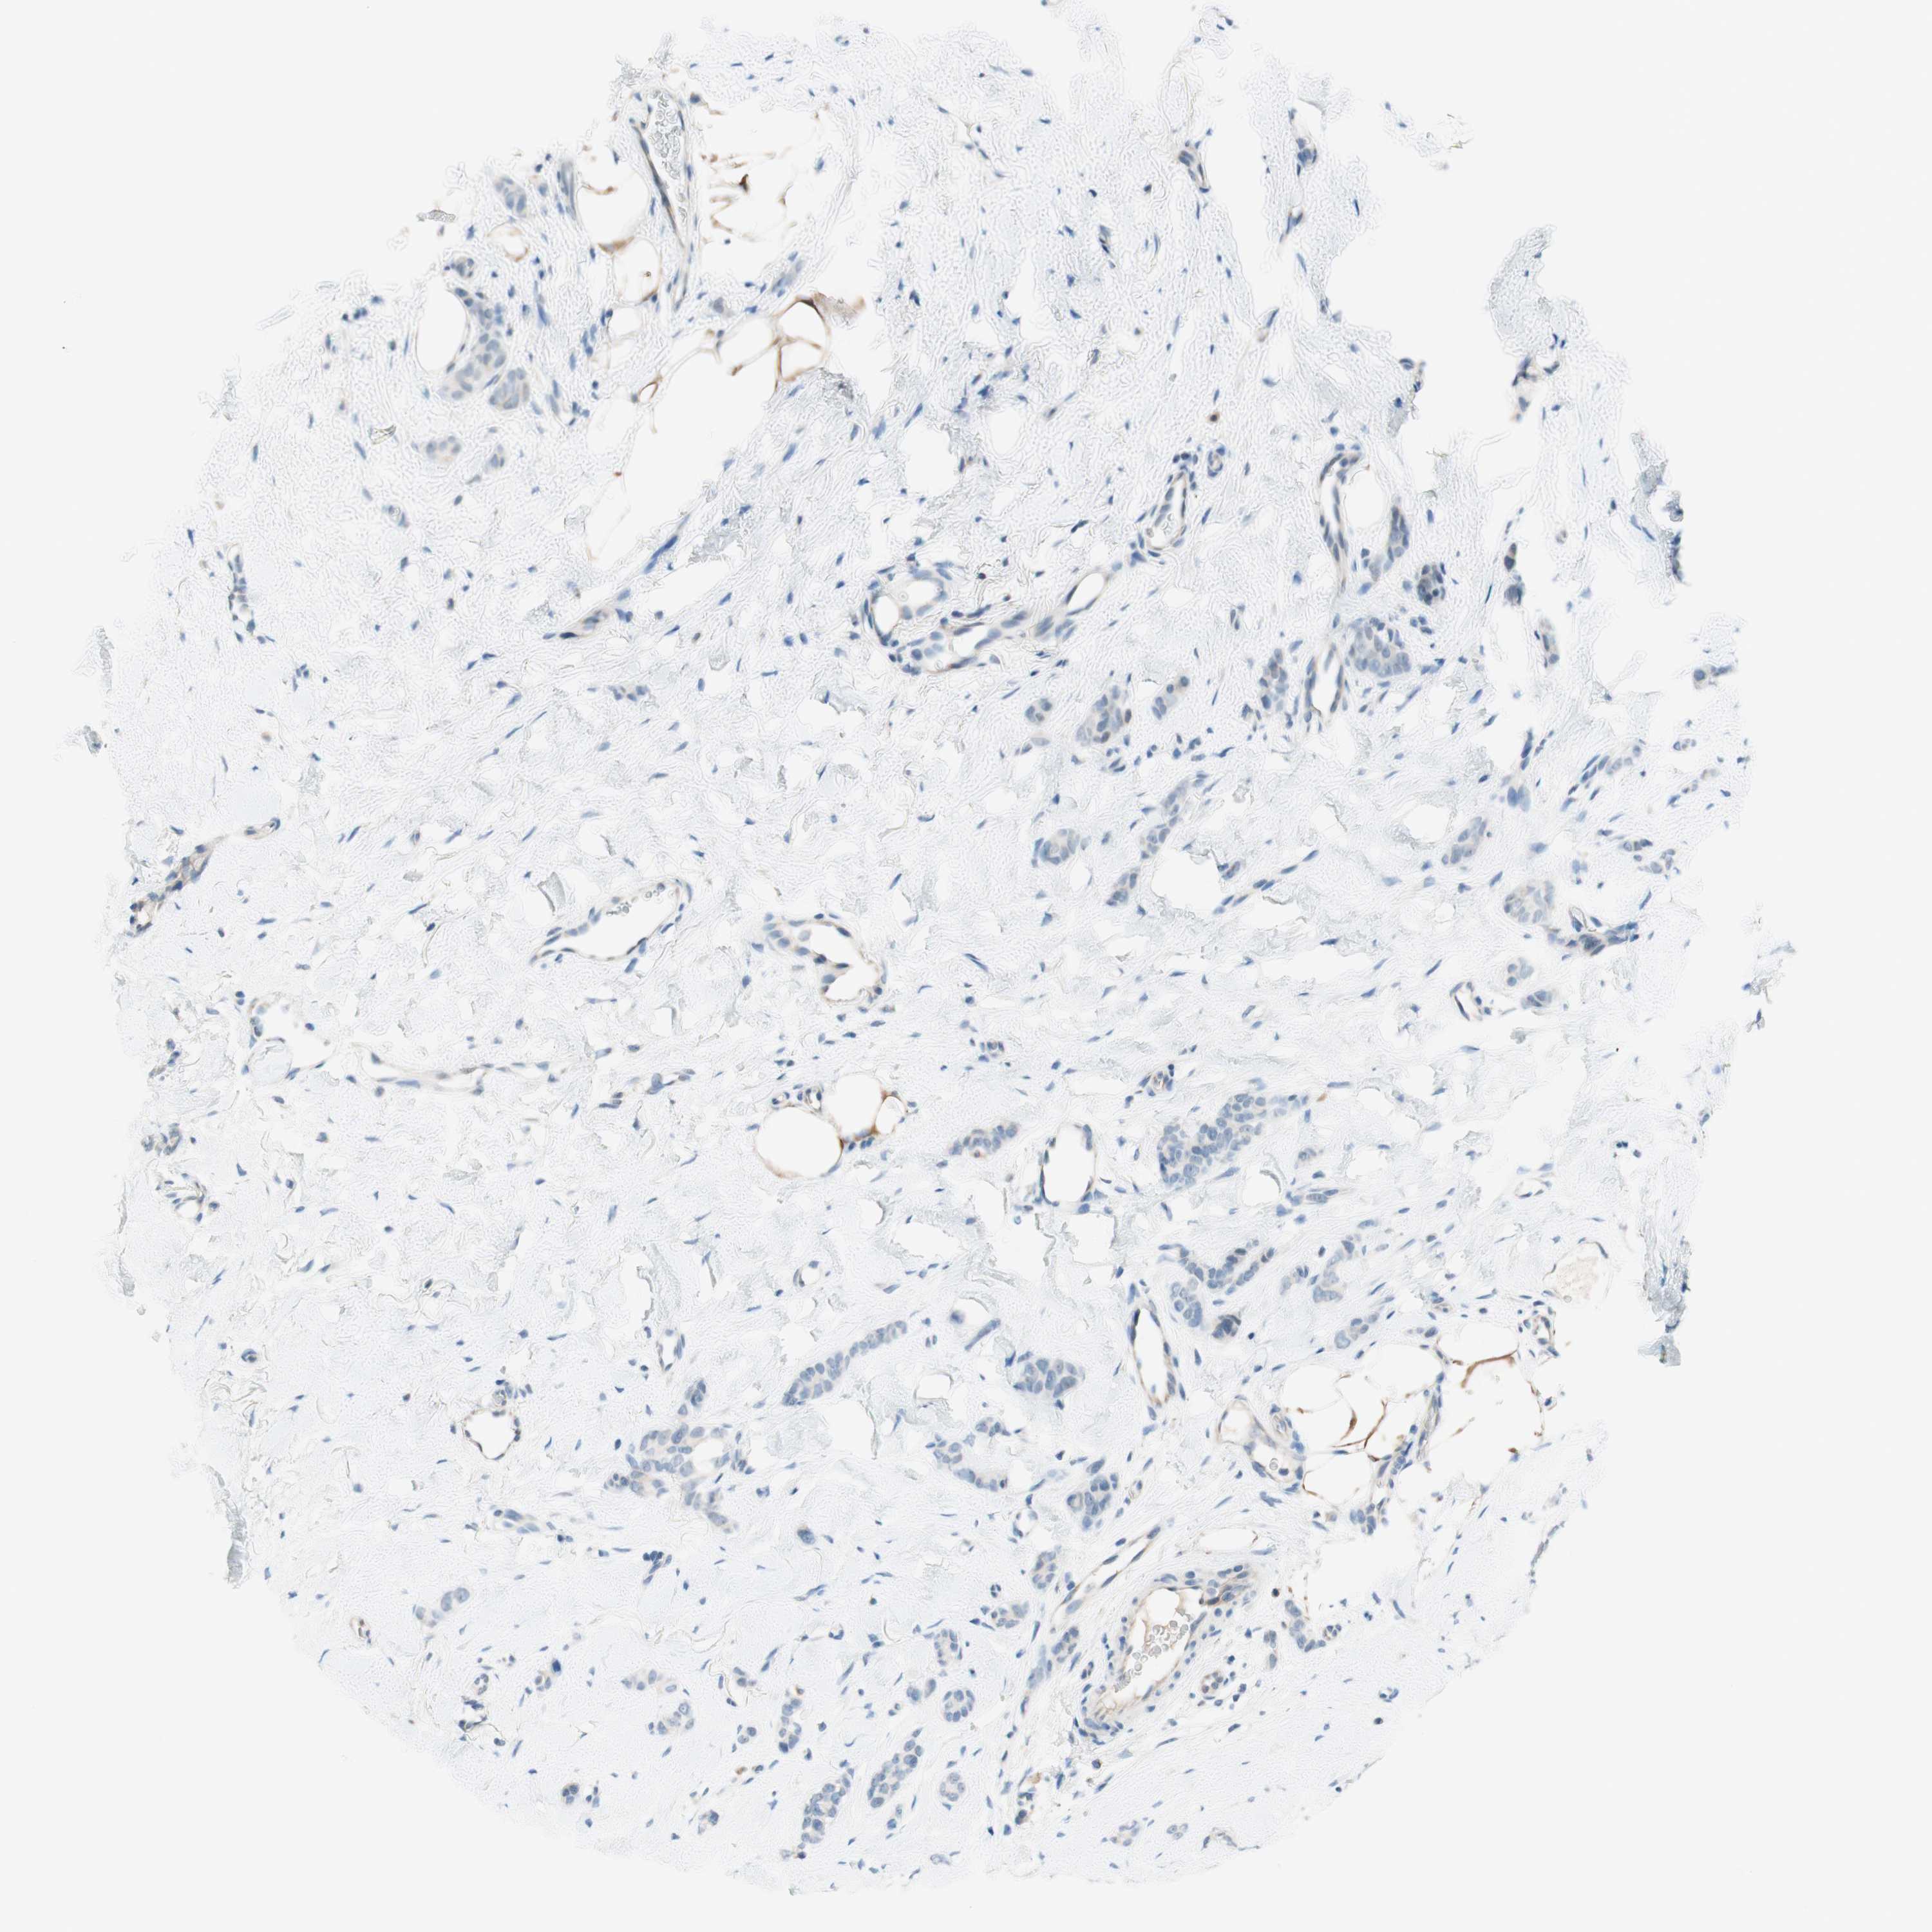

CANCER BREAST CANCER Show tissue menu

BRCA TCGA BRCA VALIDATION PROTEIN EXPRESSION